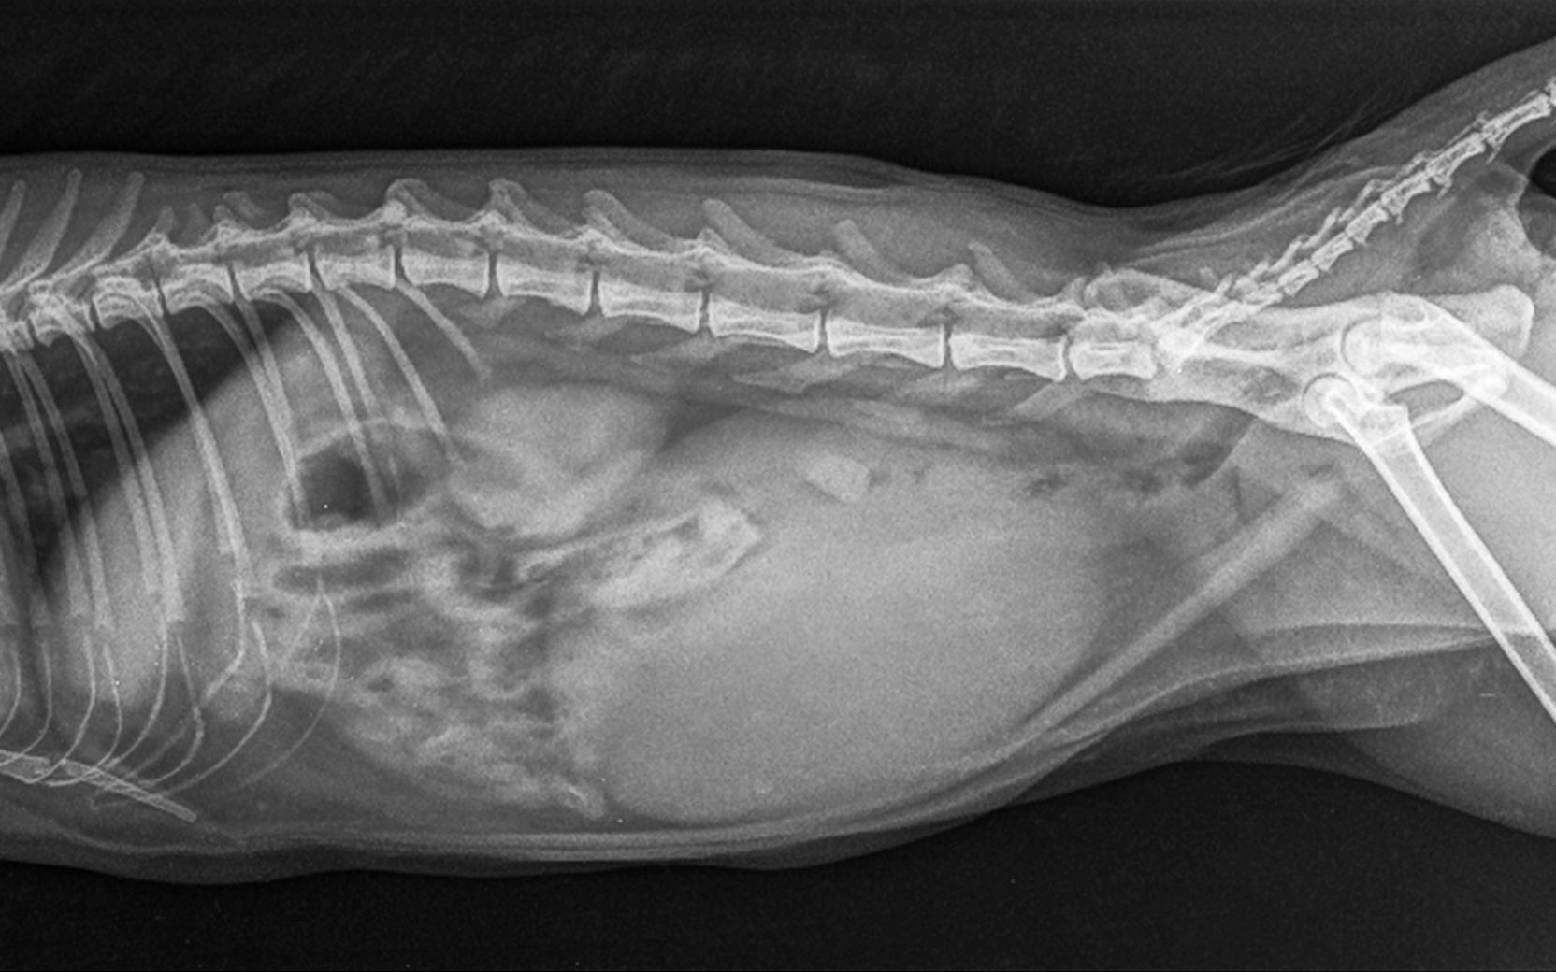

The veterinarian can usually make an initial diagnosis after taking a detailed preliminary report and performing a clinical examination. An ultrasound examination can confirm the diagnosis and reveal the cause of the narrowing. X-rays can also provide clues as to the cause of the disease. A blood test provides valuable information about the patient's general state of health and organ function, with kidney values being particularly important here. It is also always advisable to check blood values before anesthesia or surgery.